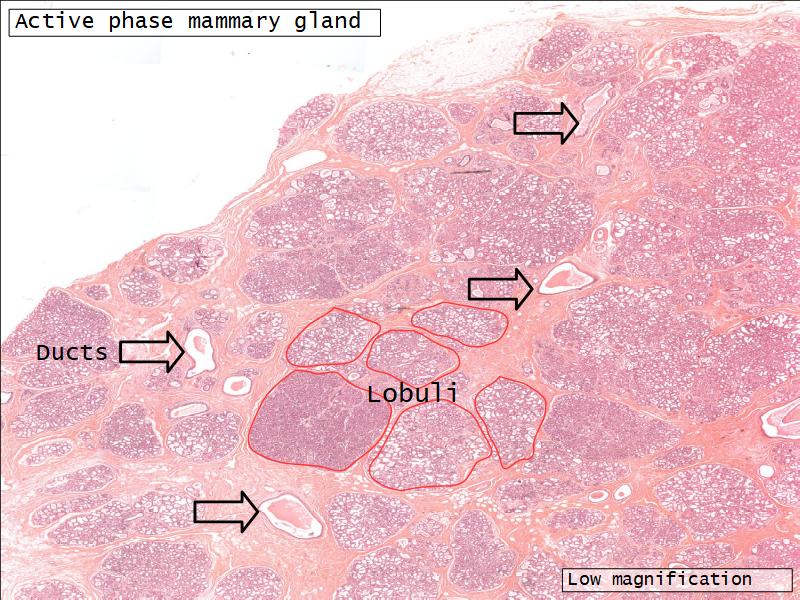

Two stages

- Resting

- Active

Resting and active

Describe the resting mammary gland and compare with the active gland.

(8)

Resting gland

- Connective tissue dominate

- More adipose tissue

- Glandular tissue reduced

Active gland

- Terminal ducts expand

- Forms alveoli

- Connective tissue reduced

- Adipose tissue reduced

- Glandular tissue dominate